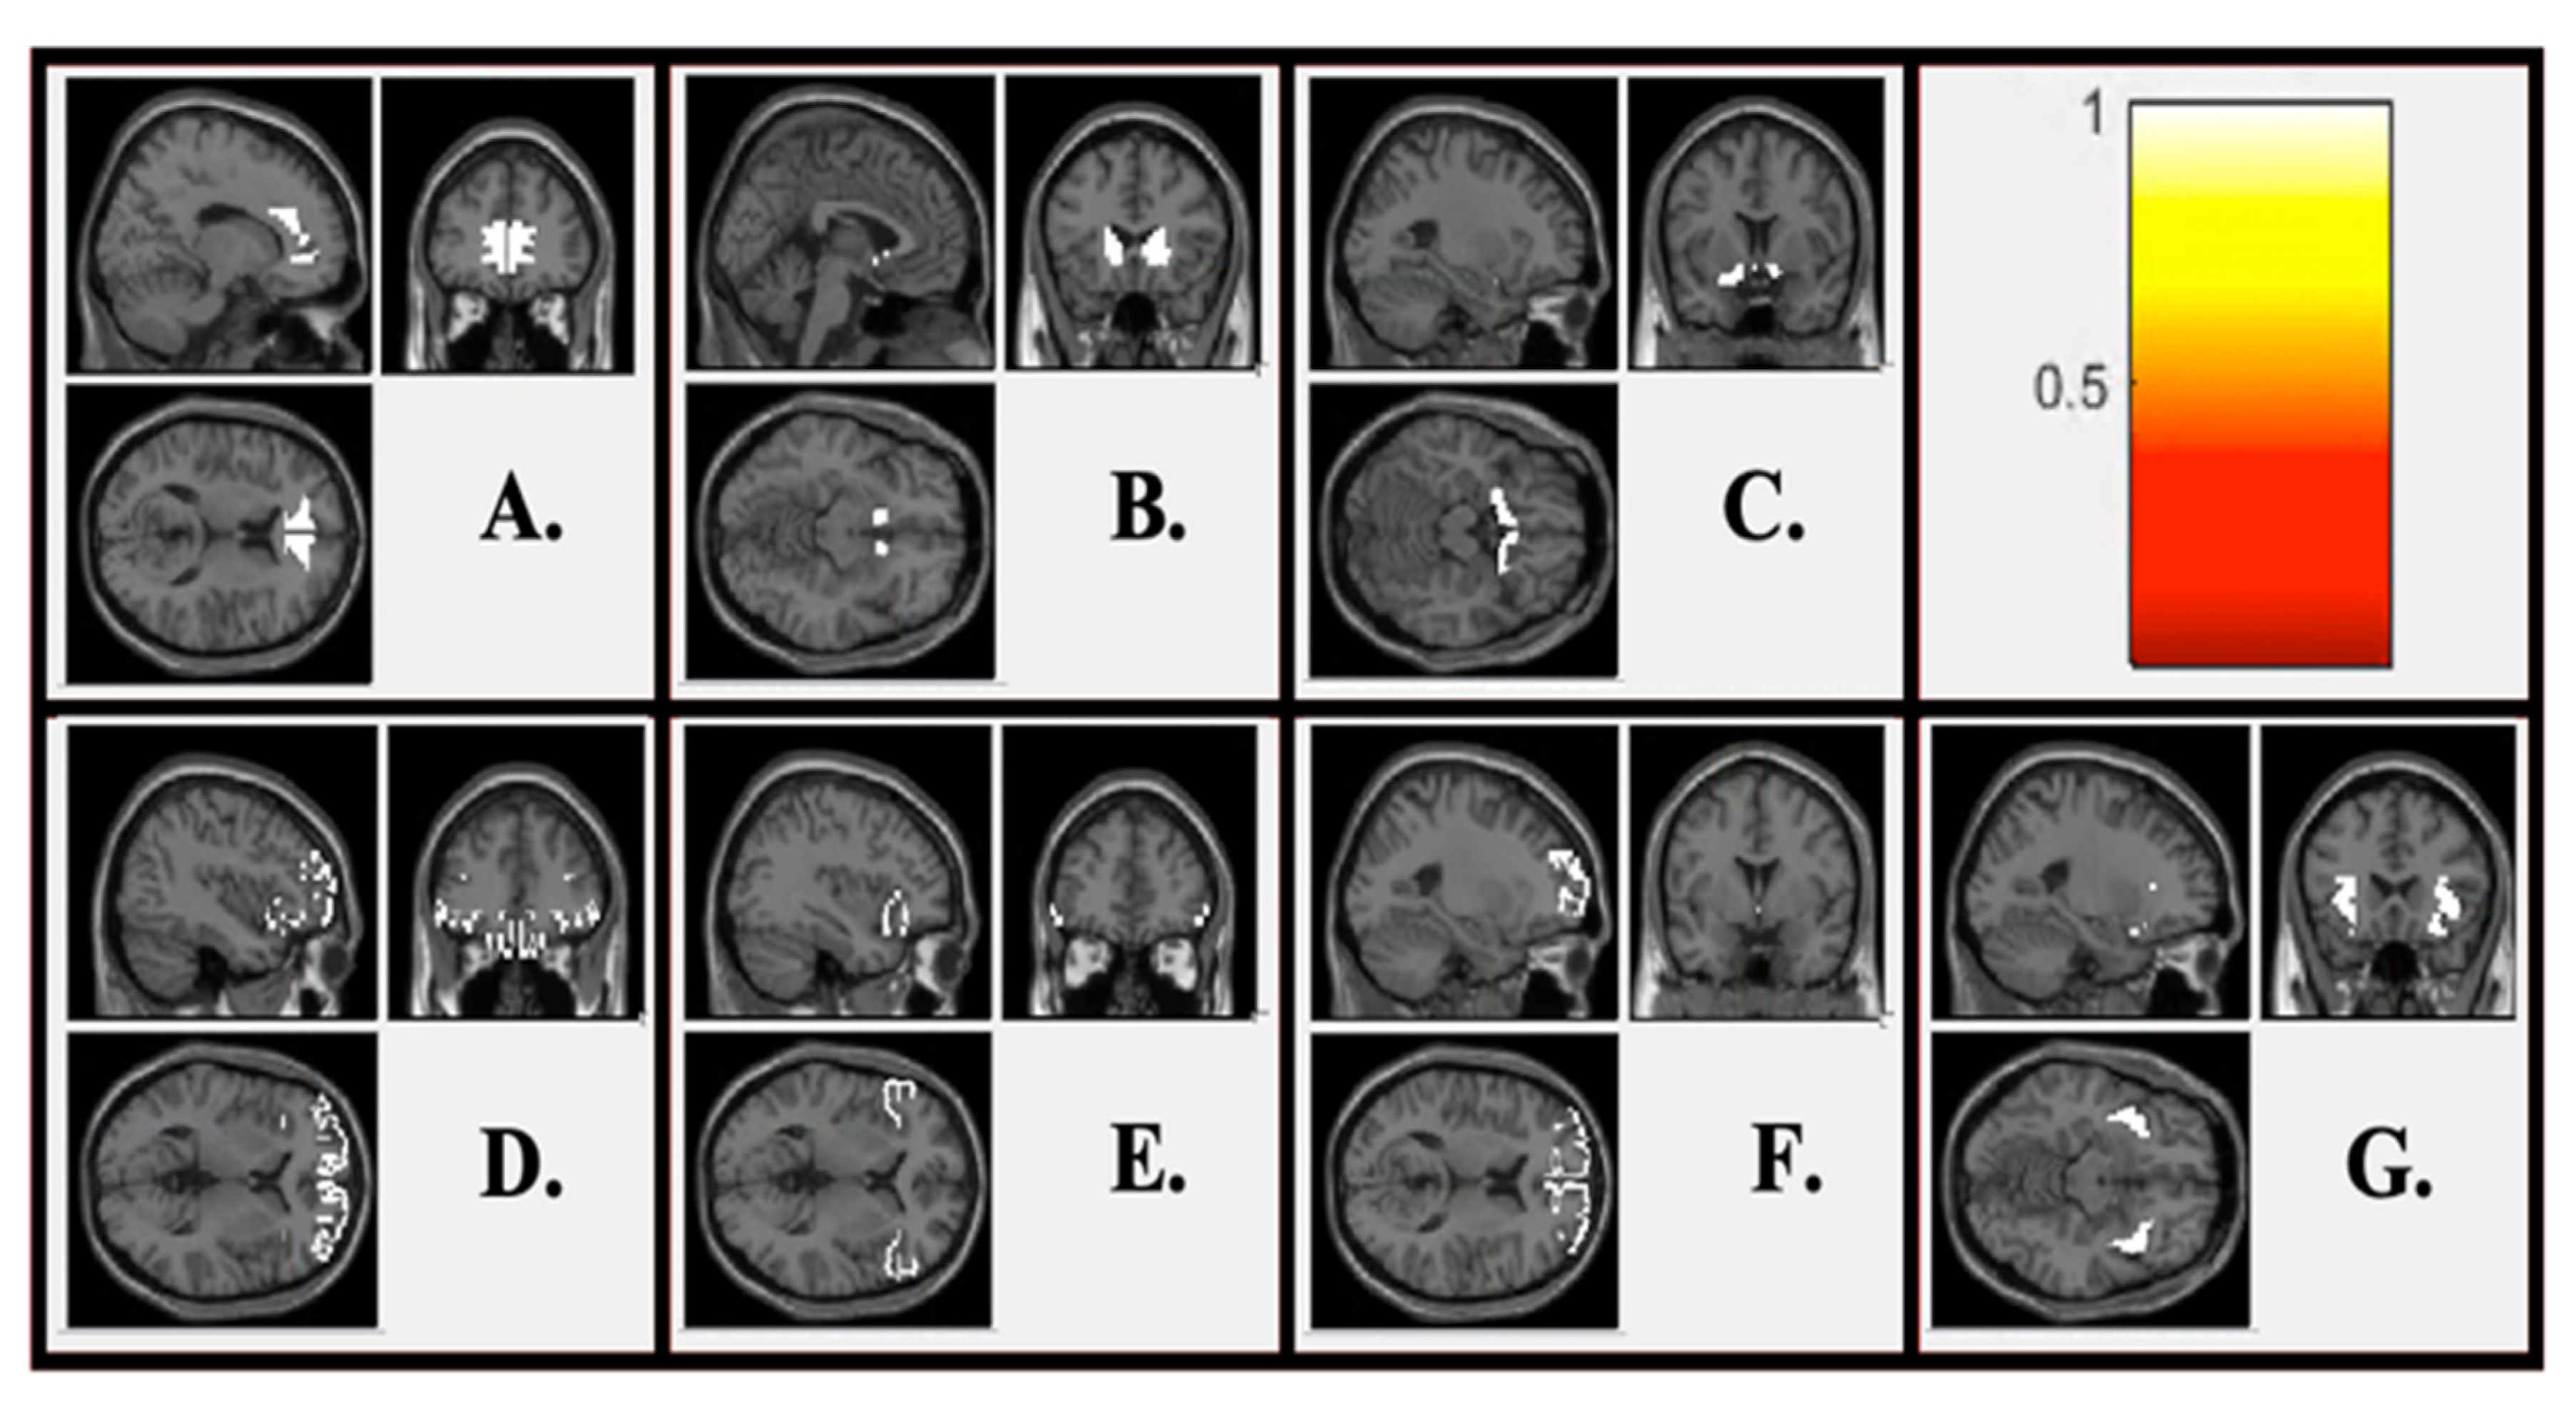

2.4.2. Description of Regions of Interest (ROIs)

2.4.3. ROI Analyses

2.4.4. Exploratory Connectivity Analyses